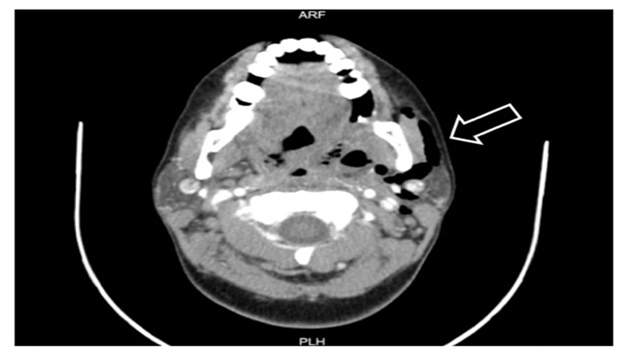

Our ENT clinic at Saudi German Hospital received a patient who had endured a record number of acute tonsillitis attacks. We examined this 40-year-old female and found red swollen tonsils. The diagnosis confirmed that she was suffering from chronic tonsillitis. Preoperative examinations including laboratory investigations and electrocardiography were normal; therefore, the patient was admitted and a tonsillectomy was performed under general anesthesia, which was induced by protocol and maintained by sevoflurane. Monopolar electrocautery dissection was used to remove the tonsils and hemostasis was attained through bipolar cautery. The operation was uneventful, and the patient recovered promptly from anesthesia, without vigorous coughing or violent neck movement; however, she began to complain of left painful submandibular swelling six hours following the operation. A marked crepitus was detected and a visible pulsation was seen on oral examination; this conformed surgical emphysema, which extended from the mandibular angle to the left side of the upper area of the neck. The patient was regularly monitored and her condition was found to be good, with minimal signs of airway compromise in the first 24 hours which then improved gradually. Computed tomography angiography of the neck was performed (Figure 1) and a small collection of serous fluid was discovered on the left operative bed, as well as marked surgical emphysema on the left side of the neck that reached superiorly to the skull base level and inferiorly to the upper mediastinum. The chest radiograph results were normal without any indication of pneumomediastinum or pneumothorax. Immediately subsequent to this diagnosis, a pressure dressing, high flow oxygen and further intravenous antibiotics were administered to the patient including Augmentin and Flagyl, steroid was not given. The patient showed significant improvement and exhibited a noticeable reduction in swelling after four days. Furthermore, to assess the pharyngeal wall, a gastrografin swallow was performed, which showed no fistulous tracts or contrast leakage. A follow-up computed tomography of the neck (Figure 2) indicated a significant reduction in the volumes of the previously observed fluid and air locules. The patient was monitored at the hospital for an additional four days, and then discharged in a generally good condition.

Figure 2 Follow-up computed tomography of the neck shows reduction of the previously observed air.